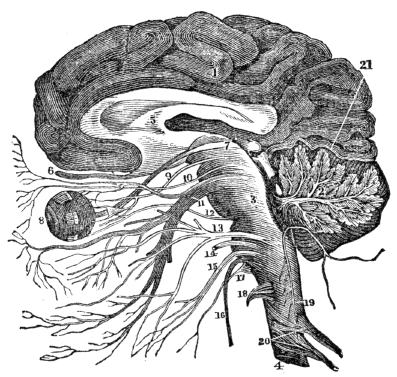

| 36. | Anatomy of the Nervous System, | 327 |

| 37. | Anatomy of the Nervous System, continued, | 340 |

| 38. | Physiology of the Nervous System, | 346 |

| 39. | Hygiene of the Nervous System, | 358 |

| 40. | Hygiene of the Nervous System, continued, | 368 |

| 41. | The Sense of Touch, | 378 |

| 42. | Anatomy of the Organs of Taste, | 384 |

| 42. | Physiology of the Organs of Taste, | 386 |

| 43. | Anatomy of the Organs of Smell, | 389 |

| 43. | Physiology of the Organs of Smell, | 391 |

| 44. | Anatomy of the Organs of Vision, | 394 |

| 45. | Physiology of the Organs of Vision, | 404 |